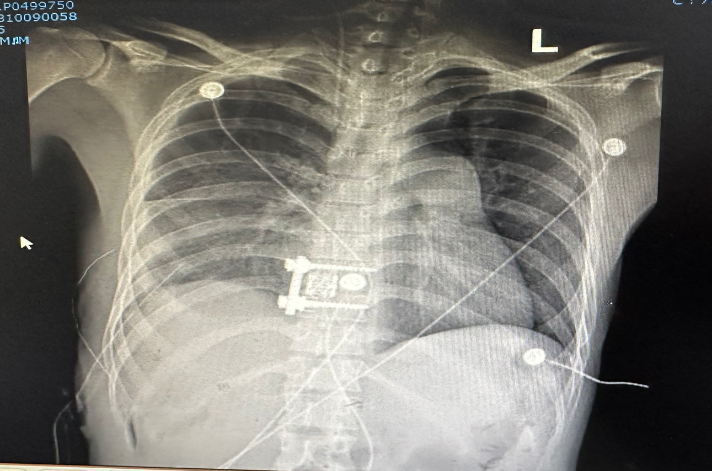

患者術(shù)前術(shù)后影像對(duì)比

胸外科主治醫(yī)生曹汐首先行胸膜板剝脫,打開胸腔見胸膜廣泛粘連,冰凍胸,手術(shù)難度極大,術(shù)中仔細(xì)分離,剝離,完整切除增厚胸膜板,暴露脊柱責(zé)任節(jié)段。第二階段后由外三科醫(yī)師周波副主任醫(yī)師、左樂主治醫(yī)師、夏長誠醫(yī)師完成胸椎結(jié)核病清除+植骨融合+內(nèi)固定術(shù)。在多學(xué)科嚴(yán)密配合下,手術(shù)順利,出血量少500ml。術(shù)后患者明顯感覺疼痛減輕,康復(fù)順利。